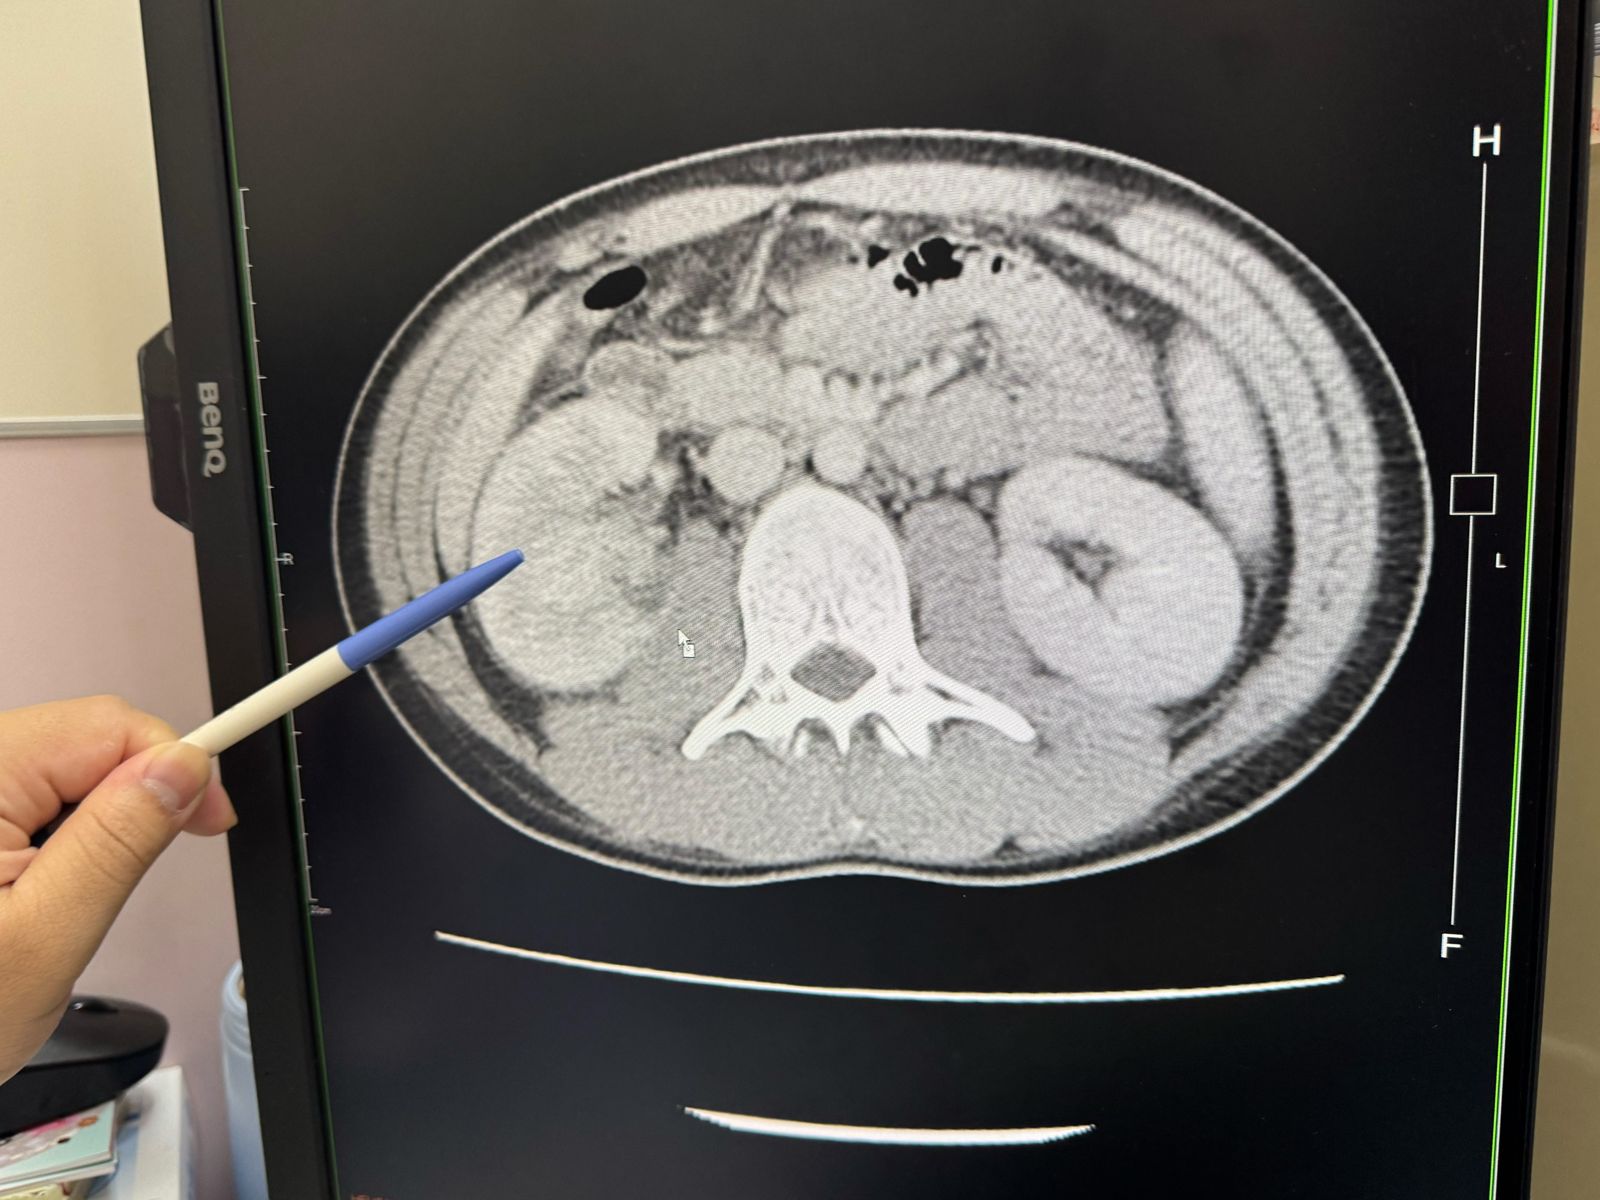

收治林男的大甲李綜合醫院泌尿科主治醫師黃品叡表示,林男因反覆發燒找不出原因、出現畏寒而自行就醫,檢查後發現,林男右邊腎臟有2個0.1公分小的結石,右腎腫大,發炎指數飆高到27mg/dL,是一般正常0.3mg/dL的90倍,馬上安排他住院治療。

林男平常幾乎不喝水,每天都喝2杯手搖飲,但還有「健康意識」,只喝半糖的飲料。不過林男又因為工作經常憋尿,才會導致腎臟結石出現血尿,被醫生診斷為急性腎盂腎炎,引發敗血症,還住進加護病房。